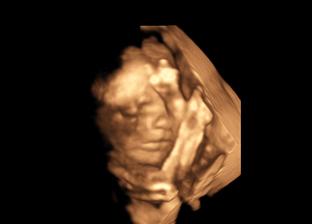

Nasa malinka v 24tt

@bambulka12 toto ako sa ukazala bol chvilkovy zazrak....inak v kuse obe ruky na tvari 🙂

@bambulka12 a diky som zabudla 🙂 no doktor vravel, ze aspon na chvilku by mohla ruky dat prec a to tak dve minuty boli z celeho 3D 🙂